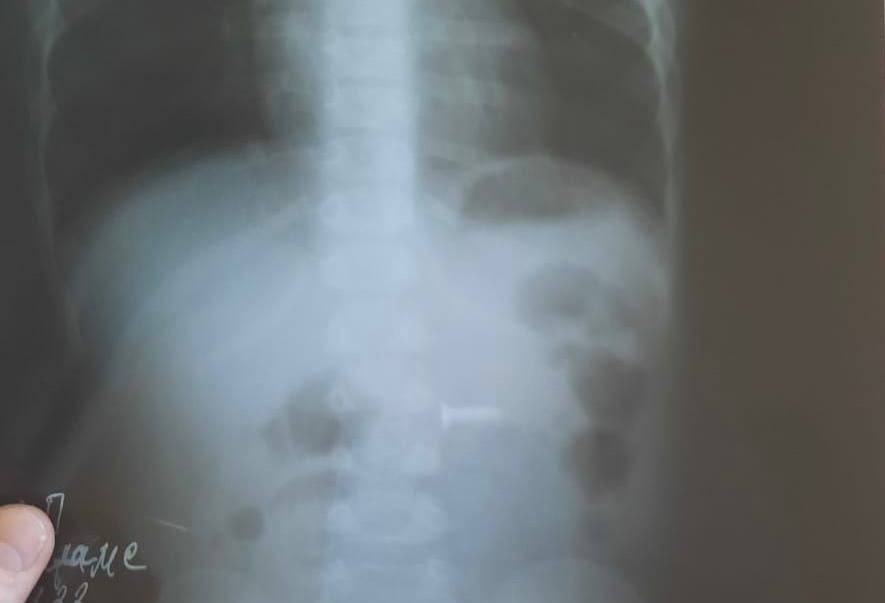

Уфимские врачи извлекли из желудка маленького ребенка саморез. Об этом в своем телеграм-канале рассказал министр здравоохранения Башкирии Айрат Рахматуллин.По информации источника, годовалый ребенок проглотил винт в то время, пока родители отвлеклись. После того, как взрослые заметили, что ребенку плохо, они сразу вызвали скорую и ребенка госпитализировали. Рентген показал наличие у ребенка в брюшной полости инородного предмета.

Врачи с помощью гастороскопии вытащили из органа малыша саморез. В настоящее время жизни и здоровью ребенка ничего не угрожает. Своевременное оказание медицинской помощи предотвратило осложнения. Теги: